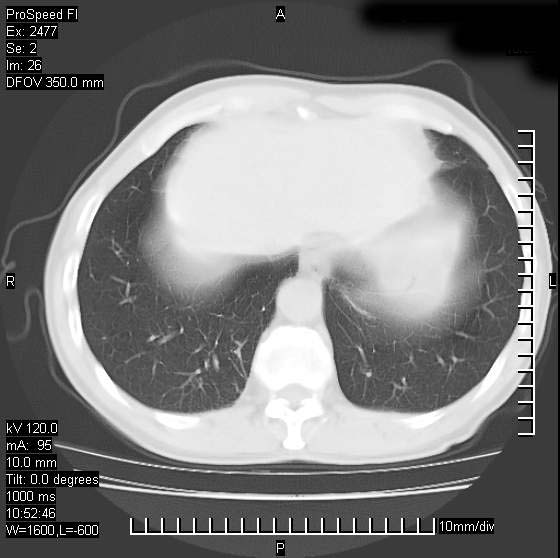

以下是引用天南地北在2007-10-9 14:29:00的发言:[br]1:右上肺结核[br]2:右肺下叶肿块:不支持肺癌,首先考虑炎性病变-肺脓疡可能性大[br]理由:1:临床病史支持,肺脓肿症状不明显应该是不规则服药造成。[br] 2:肿块边缘模糊,周围可见炎性渗出,长毛刺,内见支气管征,不过有点不规则。[br] 我感觉下肺癌这个诊断有点偏左,建议积极抗炎治疗后复查

以下是引用卜一在2007-10-9 15:55:00的发言:[br][br] [br] 1:右上肺结核[br]2:右肺下叶肿块:不支持肺癌,首先考虑炎性病变-肺脓疡可能性大[br]理由:1:临床病史支持,肺脓肿症状不明显应该是不规则服药造成。[br] 2:肿块边缘模糊,周围可见炎性渗出,长毛刺,内见空气支气管征,不过有点不规则。[br] 我感觉下肺癌这个诊断有点偏左,建议积极抗炎治疗后复查![br]支持! [br] [br] [br]

以下是引用wxy7406在2007-10-9 21:02:00的发言:[br]结合临床病史首先考虑感染性病变,但周围型肺癌不能除外,1.患者年龄偏大2.临床有咯血3.(也觉得是最重要的一点)病灶内有偏心性空洞。

以下是引用王仕学在2007-10-9 13:48:00的发言:[br]右下肺周围性肺癌可能性大,最好活检吧

以下是引用hhcckk在2007-10-9 15:18:00的发言:[br]右上肺病灶考虑结核,病灶多种形态并存(纤维化、增殖性病灶并存)[br]右下肺病灶比较难说,个人意见更趋向于“天南地北”的诊断----肺脓肿[br]1、病人有明显的寒战,高热,肿瘤病人很少出现[br]2、病灶周围的肺纹理走向柔和,没有肿瘤病灶常见的集束征[br]3、病灶边缘的毛刺较长,恶性肿瘤多为短毛刺[br]痰中血丝和病人的年龄是两个不利于良性肿块的因素,建议早点活检

以下是引用ydx_74在2007-10-9 15:53:00的发言:[br]右上肺结核,右下中心性肺癌可能大,肺门淋巴结肿大。